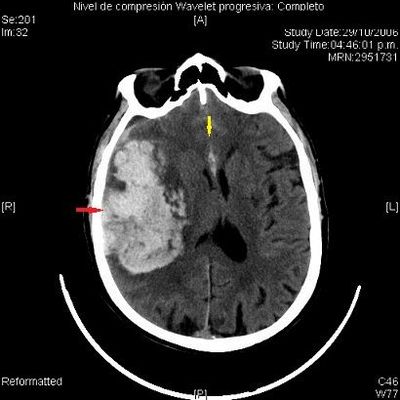

Question

que tipo de hemorragia cerebral es?

Answer

Hemorragía subaracnoidea.

hematoma subdural.

hematoma epidural.

hemorragia intraparenquimatosa.

hematoma subgaleal